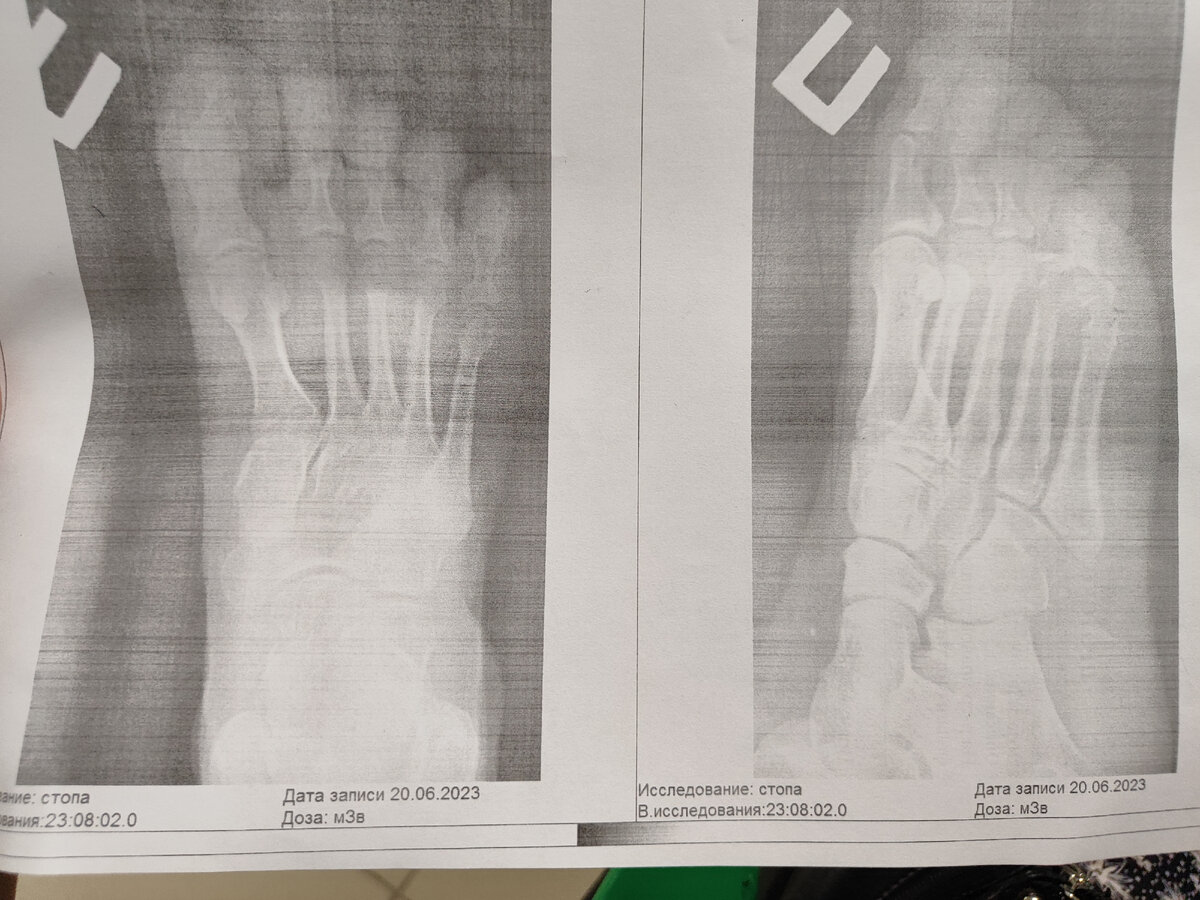

Перелом, звучало как приговор... С небольшим смещением. Только мизинца. Казалось бы, ерунда. Я, даже хожу, просто больно и не наступаю полностью на стопу с участием пальцев. С непривычки пока выглядит так себе.. Опять взяла костыль.

Наверное, это смешно, что пальчик болит, но это больно. Меня предупредили, что болеть будет в среднем месяц. Может отечь, печь. От правильности срастания зависит очень много, фактически вплоть до возможного перекоса позвоночника.

Хотели наложить прям в приёмной гипс. В итоге, медсестра зафиксировала пластырем и бинтом лодыжку с пальцем. Сошлись, что на следующий день травматолог решит как и какой гипс накладывать на палец и надо ли.

Сказал достаточно бинтовать туго и склеить пластырем три пальца. Наступать на пятку, на пальцы нельзя. Пить обезболивающее. В среднем месяц на восстановление плюс, минус.